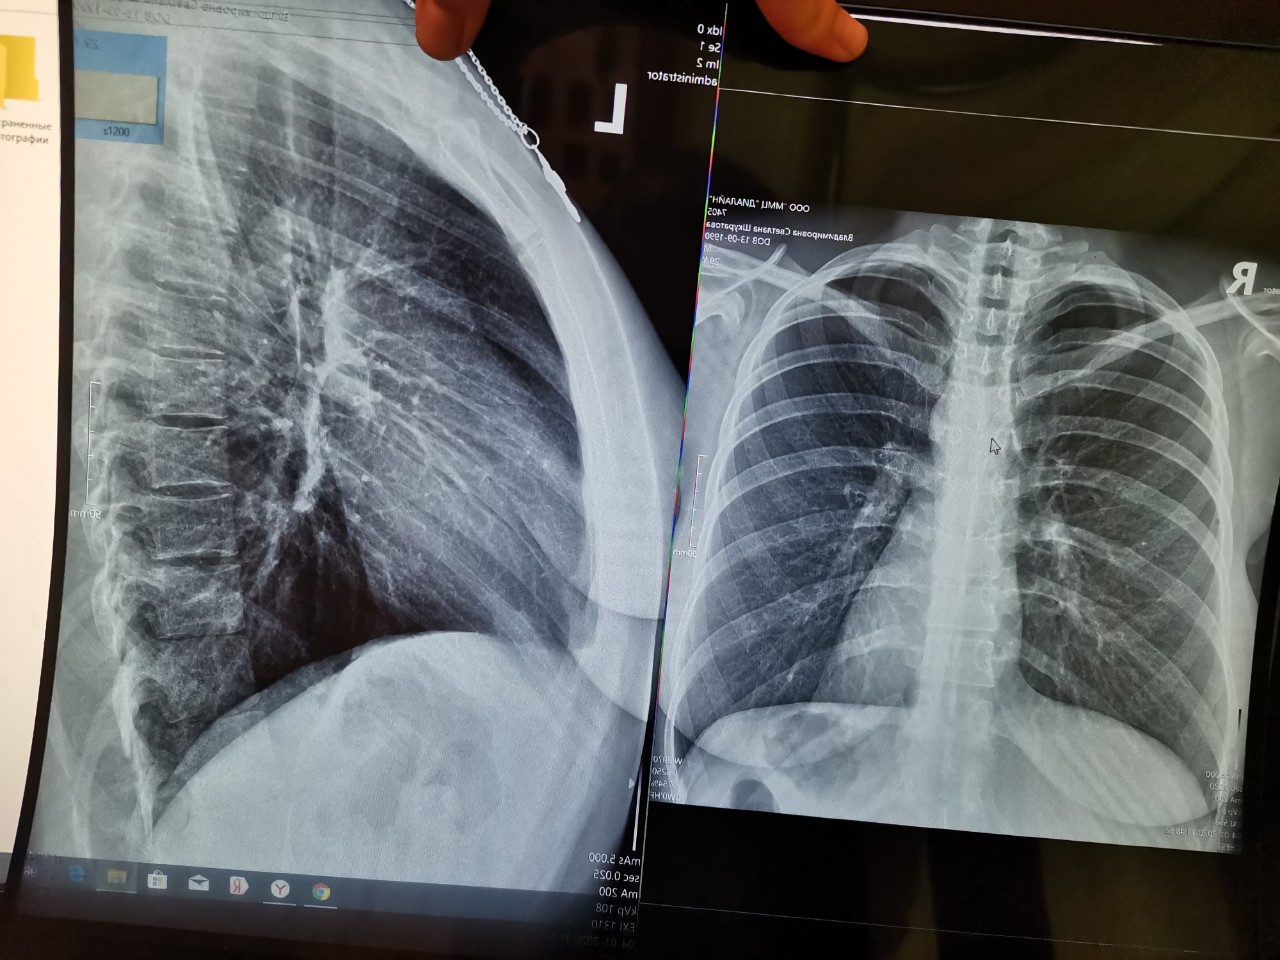

Рентген здоровых легких: примеры снимков и советы

Раздел: Сокровищница опыта